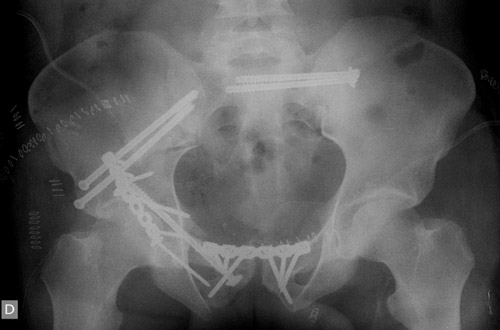

• Finally, the posterior column was reduced through a Kocher-Langenbeck approach and fixed to the anterior column with a magic screw and a posterior plate.

Second step: Posterior column fixation

Posterior column fixation